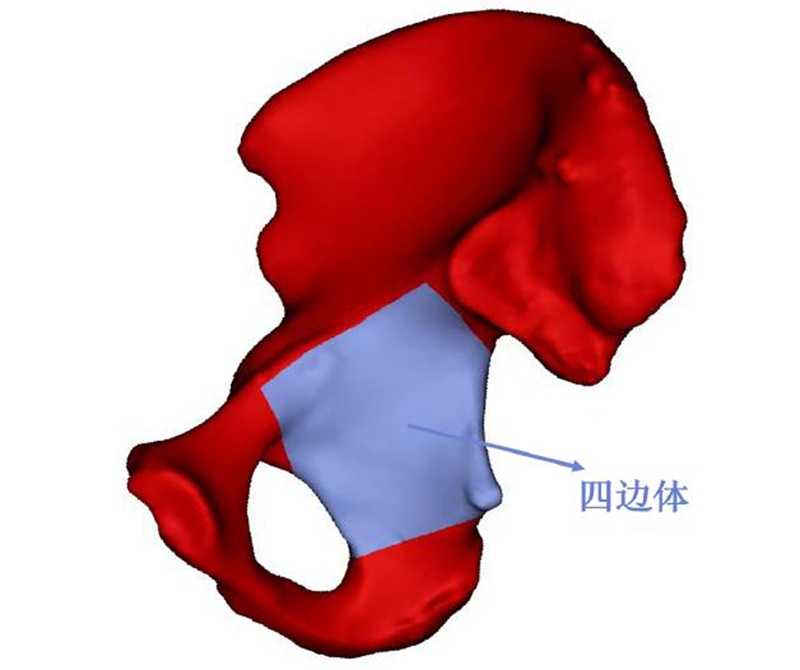

目前普遍认为,四边体的解剖界限是:上界为弓状线,下界为坐骨垂直体底部坐骨结节上缘,前界为闭孔后缘,后界为坐骨大切迹(图1)。从生物力学特性上看,髋臼窝顶部是髋臼的主要负重区,四边体是负重区的重要组成部分,具有维持股骨头与主要负重区的接触、防止股骨头向内侧移位突入盆腔的作用。人体在站立位时,负重力线由L5、骶骨经骶髂关节下传至四边体,经阻挡作用,股骨头滑移至髋臼窝顶部负重区,髋关节压力均匀分布在髋臼负重面上。四边体一旦发生骨折,就会导致关节对应关系改变、股骨头与髋臼力学失衡,引起髋臼整体力学失衡,如骨折复位不良,关节负重面减小、应力集中,则会加速关节软骨变性及创伤性关节炎的发生。

图1 四边体的解剖界限

注:上界为弓状线,下界为坐骨垂直体底部坐骨结节上缘,前界为闭孔后缘,后界为坐骨大切迹。